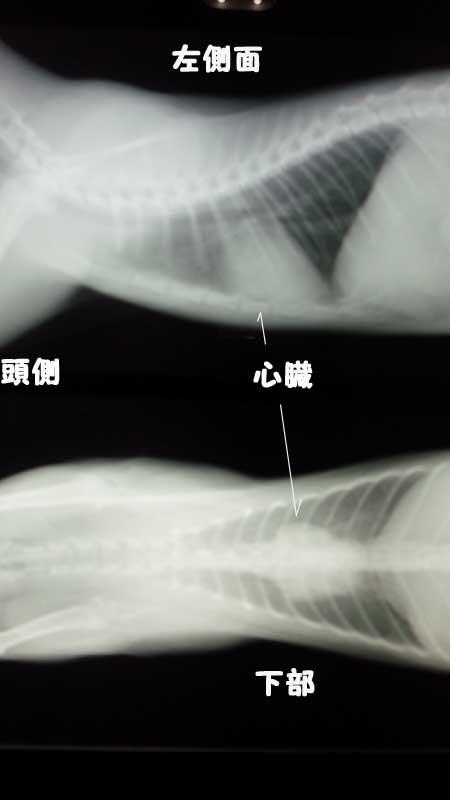

これは、セナちゃんが避妊手術の時に撮影したレントゲンです。

心臓の形がハート型ポイ感じです。

心臓がハート型になるとバレンタインハートと言って「猫の肥大型心筋症」の疑いがあります。

この時はまだ子猫でしたのハッキリした事が解らないとのことで半年後に再検査となりました。